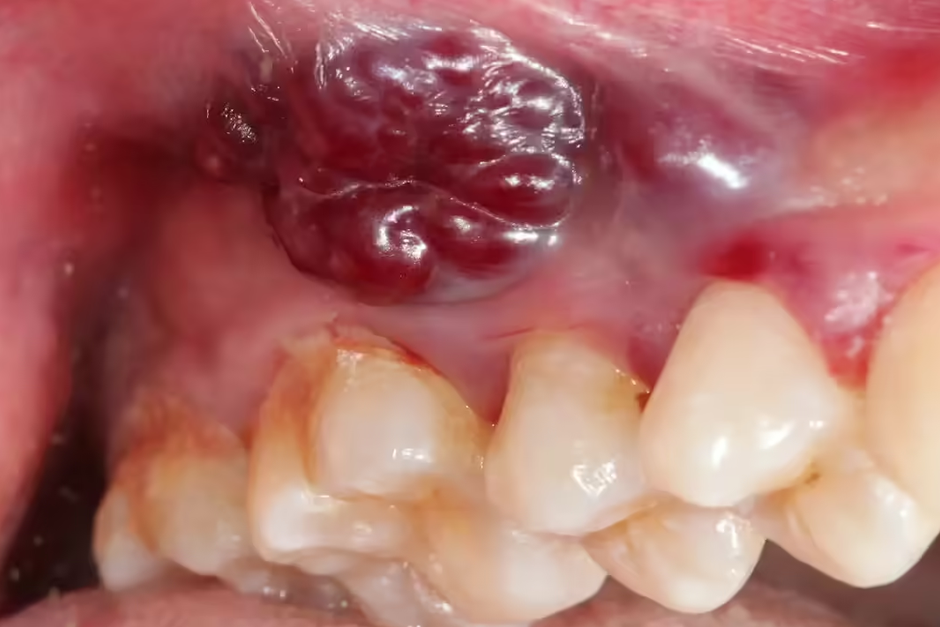

Perhaps the most potent and frequently ignored early warning sign of oral cancer is a persistent, non-healing mouth ulcer. Most common mouth ulcers are aphthous ulcers or those caused by accidental bites or trauma; these typically heal within one to two weeks. However, an ulcer that lingers for more than two weeks, despite conventional home remedies or over-the-counter treatments, demands immediate medical attention.

A suspicious ulcer often presents with distinct characteristics: it might be painless in its early stages, which unfortunately leads to complacency. It may have irregular or raised, hardened borders, and its base might appear red, white, or mixed. Common locations for such ulcers include the tongue (especially the sides), the floor of the mouth, the inner cheeks, and the soft palate. Beyond ulcers, any persistent white patch (leukoplakia), red patch (erythroplakia), or a lump/swelling in the mouth or throat that doesn’t resolve is equally concerning. Early detection dramatically improves treatment outcomes and survival rates, making proactive health-seeking behaviour paramount.